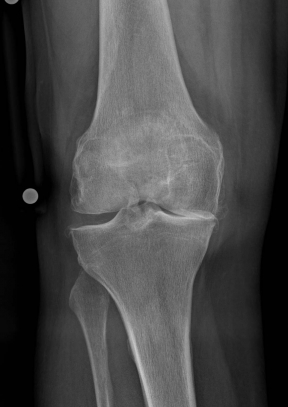

X-rays can be used to reliably diagnose the extent of joint wear. In the case of high-grade gonarthrosis, for example, the joint space and the formation of jagged edges (bone attachments, "osteophytes") as well as axial malalignment can be detected. If additional damage to the internal structures of the knee is suspected, ultrasound examination (sonography) or magnetic resonance imaging (MRI) can help clarify the situation.

Example X-ray images before and after implantation of a Persona knee prosthesis with robot.

Röntgenbild vor OP von vorn Röntgenbild vor OP von seitlich

a) präoperative Röntgenbilder des kranken Knies in 2 Ebenen